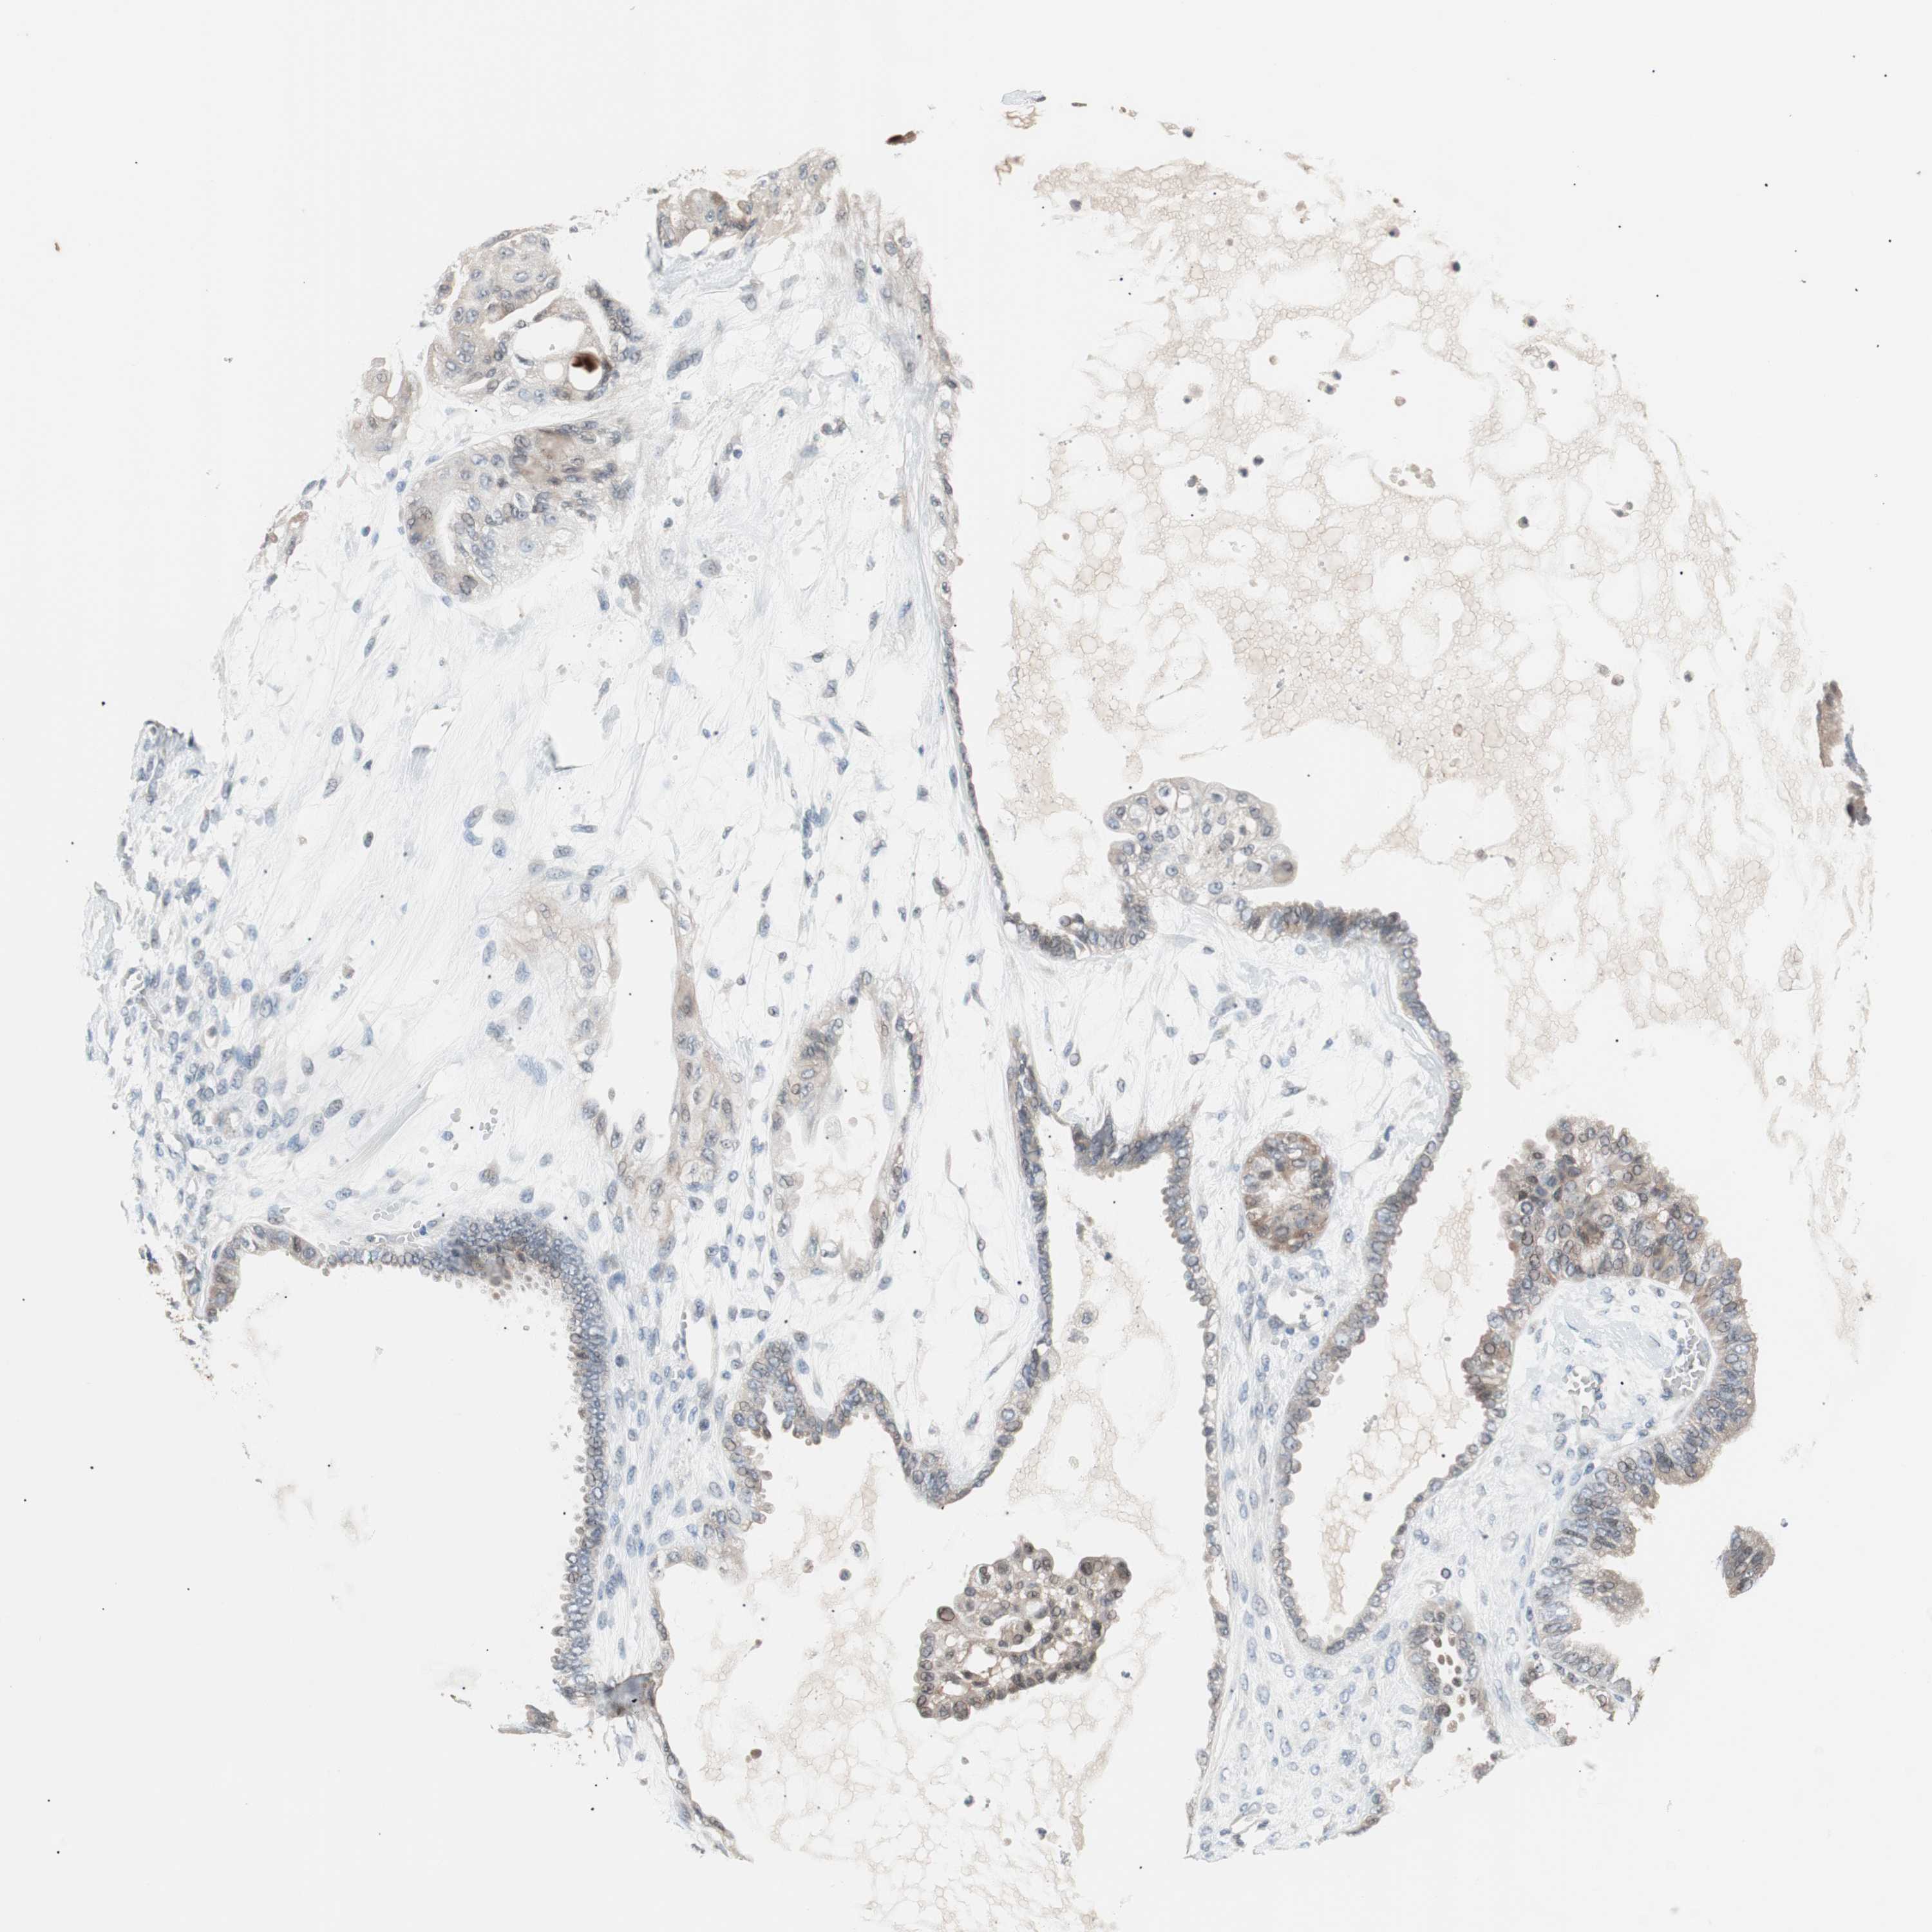

OVARIAN CANCER - Protein expressioni

A mouse-over function shows sample information and annotation data. Click on an image to view it in a full screen mode. Samples can be filtered based on level of antibody staining by selecting one or several of the following categories: high, medium, low and not detected. The assay and annotation is described here.

Note that samples used for immunohistochemistry by the Human Protein Atlas do not correspond to samples in the TCGA dataset.

Antibody stainingi

Antibody staining in the annotated cell types in the current human tissue is reported as not detected, low, medium, or high, based on conventional immunohistochemistry profiling in selected tissues. This score is based on the combination of the staining intensity and fraction of stained cells.

Each image is clickable and will lead to virtual microscopy that enables deeper exploration of all samples and also displays staining intensity scores, fraction scores and subcellular localization as well as patient and tissue information for each sample.

Antibody HPA006277

Antibody HPA006507

Antibody CAB017027

Cystadenocarcinoma, serous, NOS

Cystadenocarcinoma, mucinous, NOS

Carcinoma, endometroid

Carcinoma, NOS